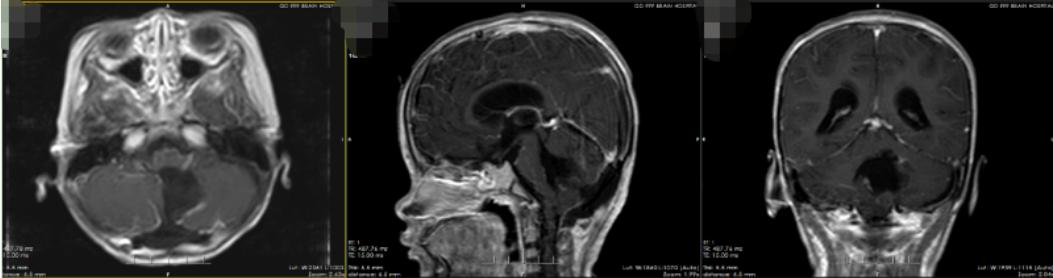

手术顺利,术后病理结果提示为毛细胞星形细胞瘤CNS WHO分级:1级。

术后影像检查(提示肿瘤全切除,脑积水及脑疝明显缓解)

术后,瑶瑶恢复良好,头痛及呕吐症状已消失,四肢可自主活动,但存在平衡障碍。经过一段时间康复治疗,瑶瑶慢慢地能在父母搀扶下走路,出院时已经能独自短距离行走。